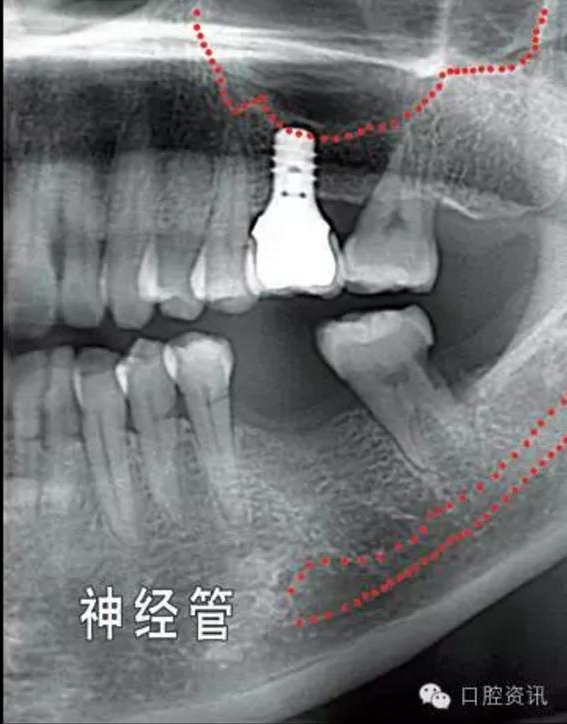

就種植手術(shù)本身而言,您頜面部一些重要結(jié)構(gòu)(例如下頜神經(jīng),上頜

竇) 的位置和形態(tài)會增加手術(shù)風(fēng)險和操作難度,為避免因手術(shù)損傷這

些重要結(jié)構(gòu),我們要求您手術(shù)前拍攝X光片作為參考,以便牙醫(yī)結(jié)合這些材料和您具體分析手術(shù)的風(fēng)險程度。

10.jpg

圖10. 可能影響種植牙手術(shù)操作的解剖結(jié)構(gòu)